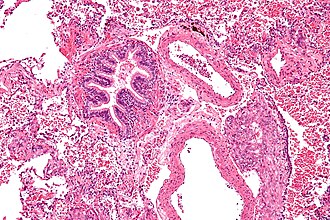

Template:Px Lymphangioleiomyomatosis. H&E stain. | |

Microscopic

Features:[6]

- Spindle cells with small nuclei + larger epithelioid cells with clear cytoplasm and round nuclei.

- Cyst formation.

- Thick arterial walls.

- Lymphangioleiomyomatosis - very low mag.jpg

LAM - very low mag. (WC)